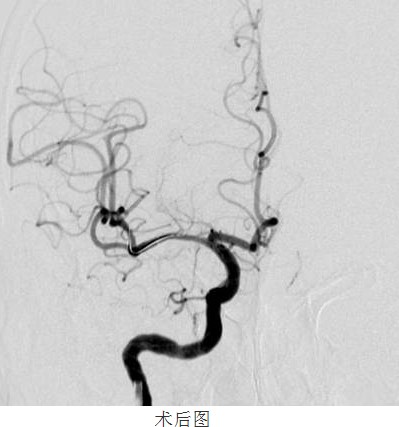

經(jīng)過(guò)數(shù)天的積極治療,患者行頭顱MRI+MRA檢查,結(jié)果和顏醫(yī)生判斷一致:右側(cè)基底節(jié)區(qū)額、頂、顳、枕葉白質(zhì)區(qū)腦梗塞,腦動(dòng)脈硬化,右側(cè)大腦中動(dòng)脈M1段不規(guī)則重度狹窄,分支血管減少。為了進(jìn)一步明確右側(cè)大腦中動(dòng)脈狹窄的程度及其他腦血管代償能力,是否達(dá)到神經(jīng)介入治療的指征,21顏津津主治醫(yī)師醫(yī)生為患者進(jìn)行了DSA腦血管造影(判斷血管狹窄的金標(biāo)準(zhǔn))進(jìn)一步證實(shí)磁共振檢查提示,右側(cè)大腦中動(dòng)脈M1近端狹窄,程度約80%,長(zhǎng)度約12cm

113號(hào)患者被送進(jìn)了DSA室內(nèi),在南方醫(yī)科大學(xué)劉亞杰教授的指導(dǎo)下,患者在靜脈全麻下(在麻醉科龍宏杰主任積極配合下),行“右側(cè)大腦中動(dòng)脈血管成形及支架植入術(shù)”。

常規(guī)準(zhǔn)備后,神經(jīng)內(nèi)科顏津津主治醫(yī)師在助手高彬醫(yī)師配合下采用Seldinger法穿刺股動(dòng)脈,置導(dǎo)管鞘、引導(dǎo)管,在導(dǎo)絲帶引下將導(dǎo)引導(dǎo)管放置右側(cè)頸內(nèi)動(dòng)脈巖部造影,后在透視下,順著造影路圖,小心將微導(dǎo)絲、微導(dǎo)管通過(guò)狹窄處并置入右側(cè)大腦中動(dòng)脈M3段,接著撤出微導(dǎo)管,順著微導(dǎo)絲置入Gateway球囊, 至狹窄部位,經(jīng)造影骨性標(biāo)志等多重定位后證實(shí)球囊位置良好,接壓力泵緩慢加壓擴(kuò)張,撤出球囊造影,顯示血管成形良好。選取Wingspan支架, 順微導(dǎo)絲將支架輸送器小心送至狹窄處,造影定位確認(rèn)支架位置準(zhǔn)確覆蓋狹窄部位,釋放支架,撤出支架輸送器,造影證實(shí)血管狹窄處成形良好,觀察10分鐘后再次造影,支架無(wú)移位,狹窄處遠(yuǎn)端血管完整,未見血管狹窄、造影劑外滲。撤除導(dǎo)絲、導(dǎo)引導(dǎo)管,患者術(shù)后24小時(shí)可下床自行活動(dòng),術(shù)后1周順利出院,生活基本恢復(fù)正常,并叮囑梁伯繼續(xù)堅(jiān)持服藥,定期復(fù)診。

“大腦中動(dòng)脈血管成形及支架植入術(shù)”為我院首例顱內(nèi)支架植入手術(shù),其順利完成,標(biāo)志著我院在神經(jīng)介入診療方面的水平又上了一個(gè)新的臺(tái)階!